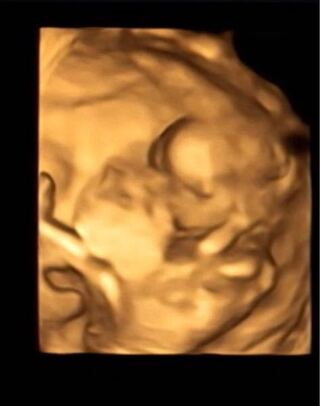

4dエコーで初めて見たわが子の顔 先生が撮った最高の1枚 たまひよ

妊娠12週目 12w0d 6d のエコー写真とエピソード 妊娠4ヶ月 Cozre コズレ 子育てマガジン

エコー写真と同じ顔 Instagram Posts Gramho Com

臨月 4dエコーと実際の顔はどこまで似てるのか Rins Happy Life

Nuimono日記 12w 4dエコーに驚く